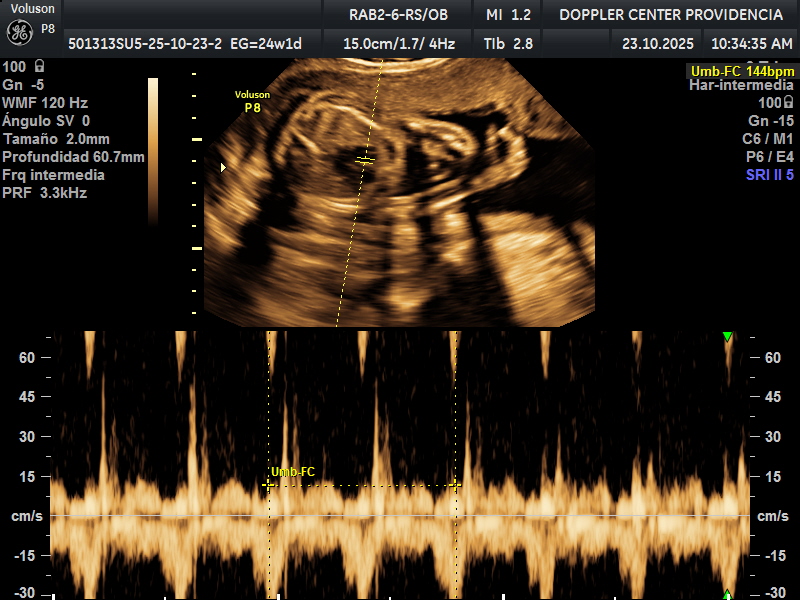

Es una técnica especializada de ultrasonido que utiliza el efecto Doppler para evaluar el flujo sanguíneo en el sistema circulatorio del feto y la madre durante el embarazo.

Se usa principalmente para evaluar el flujo sanguíneo en la placenta, el cordón umbilical y los vasos sanguíneos de la madre y el feto. Esto proporciona información valiosa sobre la salud del embarazo y la circulación fetal.

• Eco Doppler 22-24 semanas